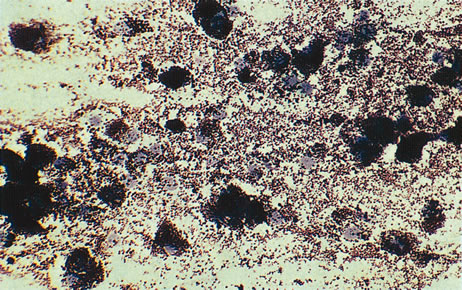

Figure 16 shows a case of what clinically and ultrasonographically appeared to be a uveal melanoma. The FNAB specimen revealed a cellular pattern that was diagnostic of a primary carcinoid (Fig. 17), and the patient responded dramatically with 40 gray of photon radiation. Figure 18 shows the FNAB cytopathology of a typical epithelioid choroidal melanoma; in contrast, a smear of a spindle cell tumor has spindle-shaped cytoplasm and smaller nuclei. Figure 19 shows a benign pigmented mass, such as a retinal pigment epithelial proliferation or a melanocytoma. In contrast to a melanoma, this type of mass has much larger pigment granules and benign cytomorphologic detail. In addition to standard cytopathologic FNAB evaluation, aspirated material may be used for several molecular biology studies (e.g., fluorescence in situ hybridization, comparative genomic hybridization), flow cytometry, special stains, tissue culture, and ultrastructural analyses.

Fig. 19. Fine-needle biopsy from a benign melanocytoma. In contrast to a uveal melanoma, a benign melanocytoma has pigment granules that are much larger. Its nuclear detail is also bland and lacking nucleoli.